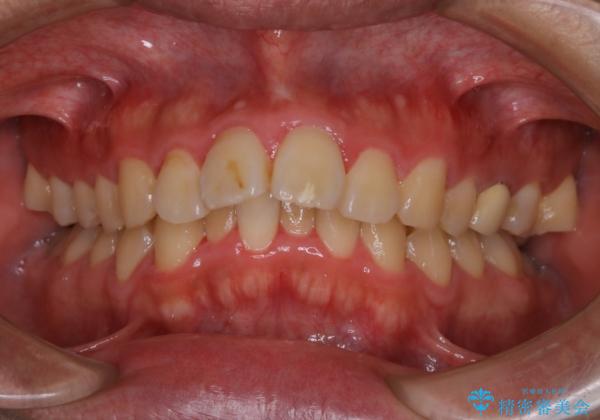

- 上顎前歯の突出感と下顎前歯のガタつきが主訴で来院されました。

出っ歯とガタつきの改善を行うには抜歯が必要と診断し、上下左右第一小臼歯を抜歯する計画を立てました。

抜歯する事で歯の移動量が大きいことからワイヤー表側矯正装置で治療を行うことになりました。

今回のような歯の移動量が大きい場合、インビザライン治療では歯が傾いてしまう場合があります。

ワイヤー治療では歯の傾きを抑えながら大きい距離の移動が可能で、かみ合わせが深くなるリスクも少ないです。